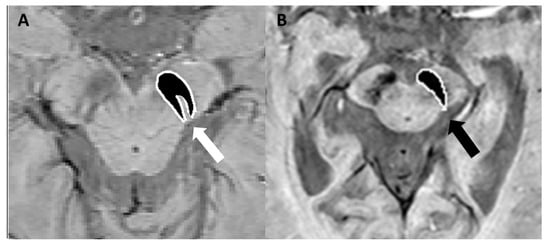

4.1. Parkinson’s Disease, Lewy Body Dementia, and Atypical Parkinsonian Syndromes

- Schwarz, S.T.; Afzal, M.; Morgan, P.S.; Bajaj, N.; Gowland, P.A.; Auer, D.P. The ‘Swallow Tail’ Appearance of the Healthy Nigrosome—A New Accurate Test of Parkinson’s Disease: A Case-Control and Retrospective Cross-Sectional MRI Study at 3T. PLoS ONE 2014, 9, e93814. [Google Scholar] [CrossRef] [PubMed]

- Cheng, Z.; He, N.; Huang, P.; Li, Y.; Tang, R.; Sethi, S.K.; Ghassaban, K.; Yerramsetty, K.K.; Palutla, V.K.; Chen, S.; et al. Imaging the Nigrosome 1 in the substantia nigra using susceptibility weighted imaging and quantitative susceptibility mapping: An application to Parkinson’s disease. NeuroImage Clin. 2020, 25, 102103. [Google Scholar] [CrossRef]

- Schmidt, M.A.; Engelhorn, T.; Marxreiter, F.; Winkler, J.; Lang, S.; Kloska, S.; Goelitz, P.; Doerfler, A. Ultra high-field SWI of the substantia nigra at 7T: Reliability and consistency of the swallow-tail sign. BMC Neurol. 2017, 17, 194. [Google Scholar] [CrossRef] [PubMed]

- Gao, P.; Zhou, P.-Y.; Li, G.; Zhang, G.-B.; Wang, P.-Q.; Liu, J.-Z.; Xu, F.; Yang, F.; Wu, X.-X. Visualization of nigrosomes-1 in 3T MR susceptibility weighted imaging and its absence in diagnosing Parkinson’s disease. Eur. Rev. Med. Pharmacol. Sci. 2015, 19, 4603–4609. [Google Scholar] [PubMed]

- Mahlknecht, P.; Krismer, F.; Poewe, W.; Seppi, K. Meta-analysis of dorsolateral nigral hyperintensity on magnetic resonance imaging as a marker for Parkinson’s disease. Mov. Disord. 2017, 32, 619–623. [Google Scholar] [CrossRef]

- Shams, S.; Fällmar, D.; Schwarz, S.; Wahlund, L.-O.; van Westen, D.; Hansson, O.; Larsson, E.-M.; Haller, S. MRI of the Swallow Tail Sign: A Useful Marker in the Diagnosis of Lewy Body Dementia? Am. J. Neuroradiol. 2017, 38, 1737–1741. [Google Scholar] [CrossRef]

- Lee, T.-W.; Chen, C.-Y.; Chen, K.; Tso, C.-W.; Lin, H.-H.; Lai, Y.-L.L.; Hsu, F.-T.; Chung, H.-W.; Liu, H.-S. Evaluation of the Swallow-Tail Sign and Correlations of Neuromelanin Signal with Susceptibility and Relaxations. Tomography 2021, 7, 107–119. [Google Scholar] [CrossRef]

- Meijer, F.J.; Steens, S.C.; van Rumund, A.; Walsum, A.-M.v.C.v.; Küsters, B.; Esselink, R.A.; Verbeek, M.M.; Bloem, B.R.; Goraj, B. Nigrosome-1 on Susceptibility Weighted Imaging to Differentiate Parkinson’s Disease from Atypical Parkinsonism: An In Vivo and Ex Vivo Pilot Study. Pol. J. Radiol. 2016, 81, 363–369. [Google Scholar] [CrossRef]